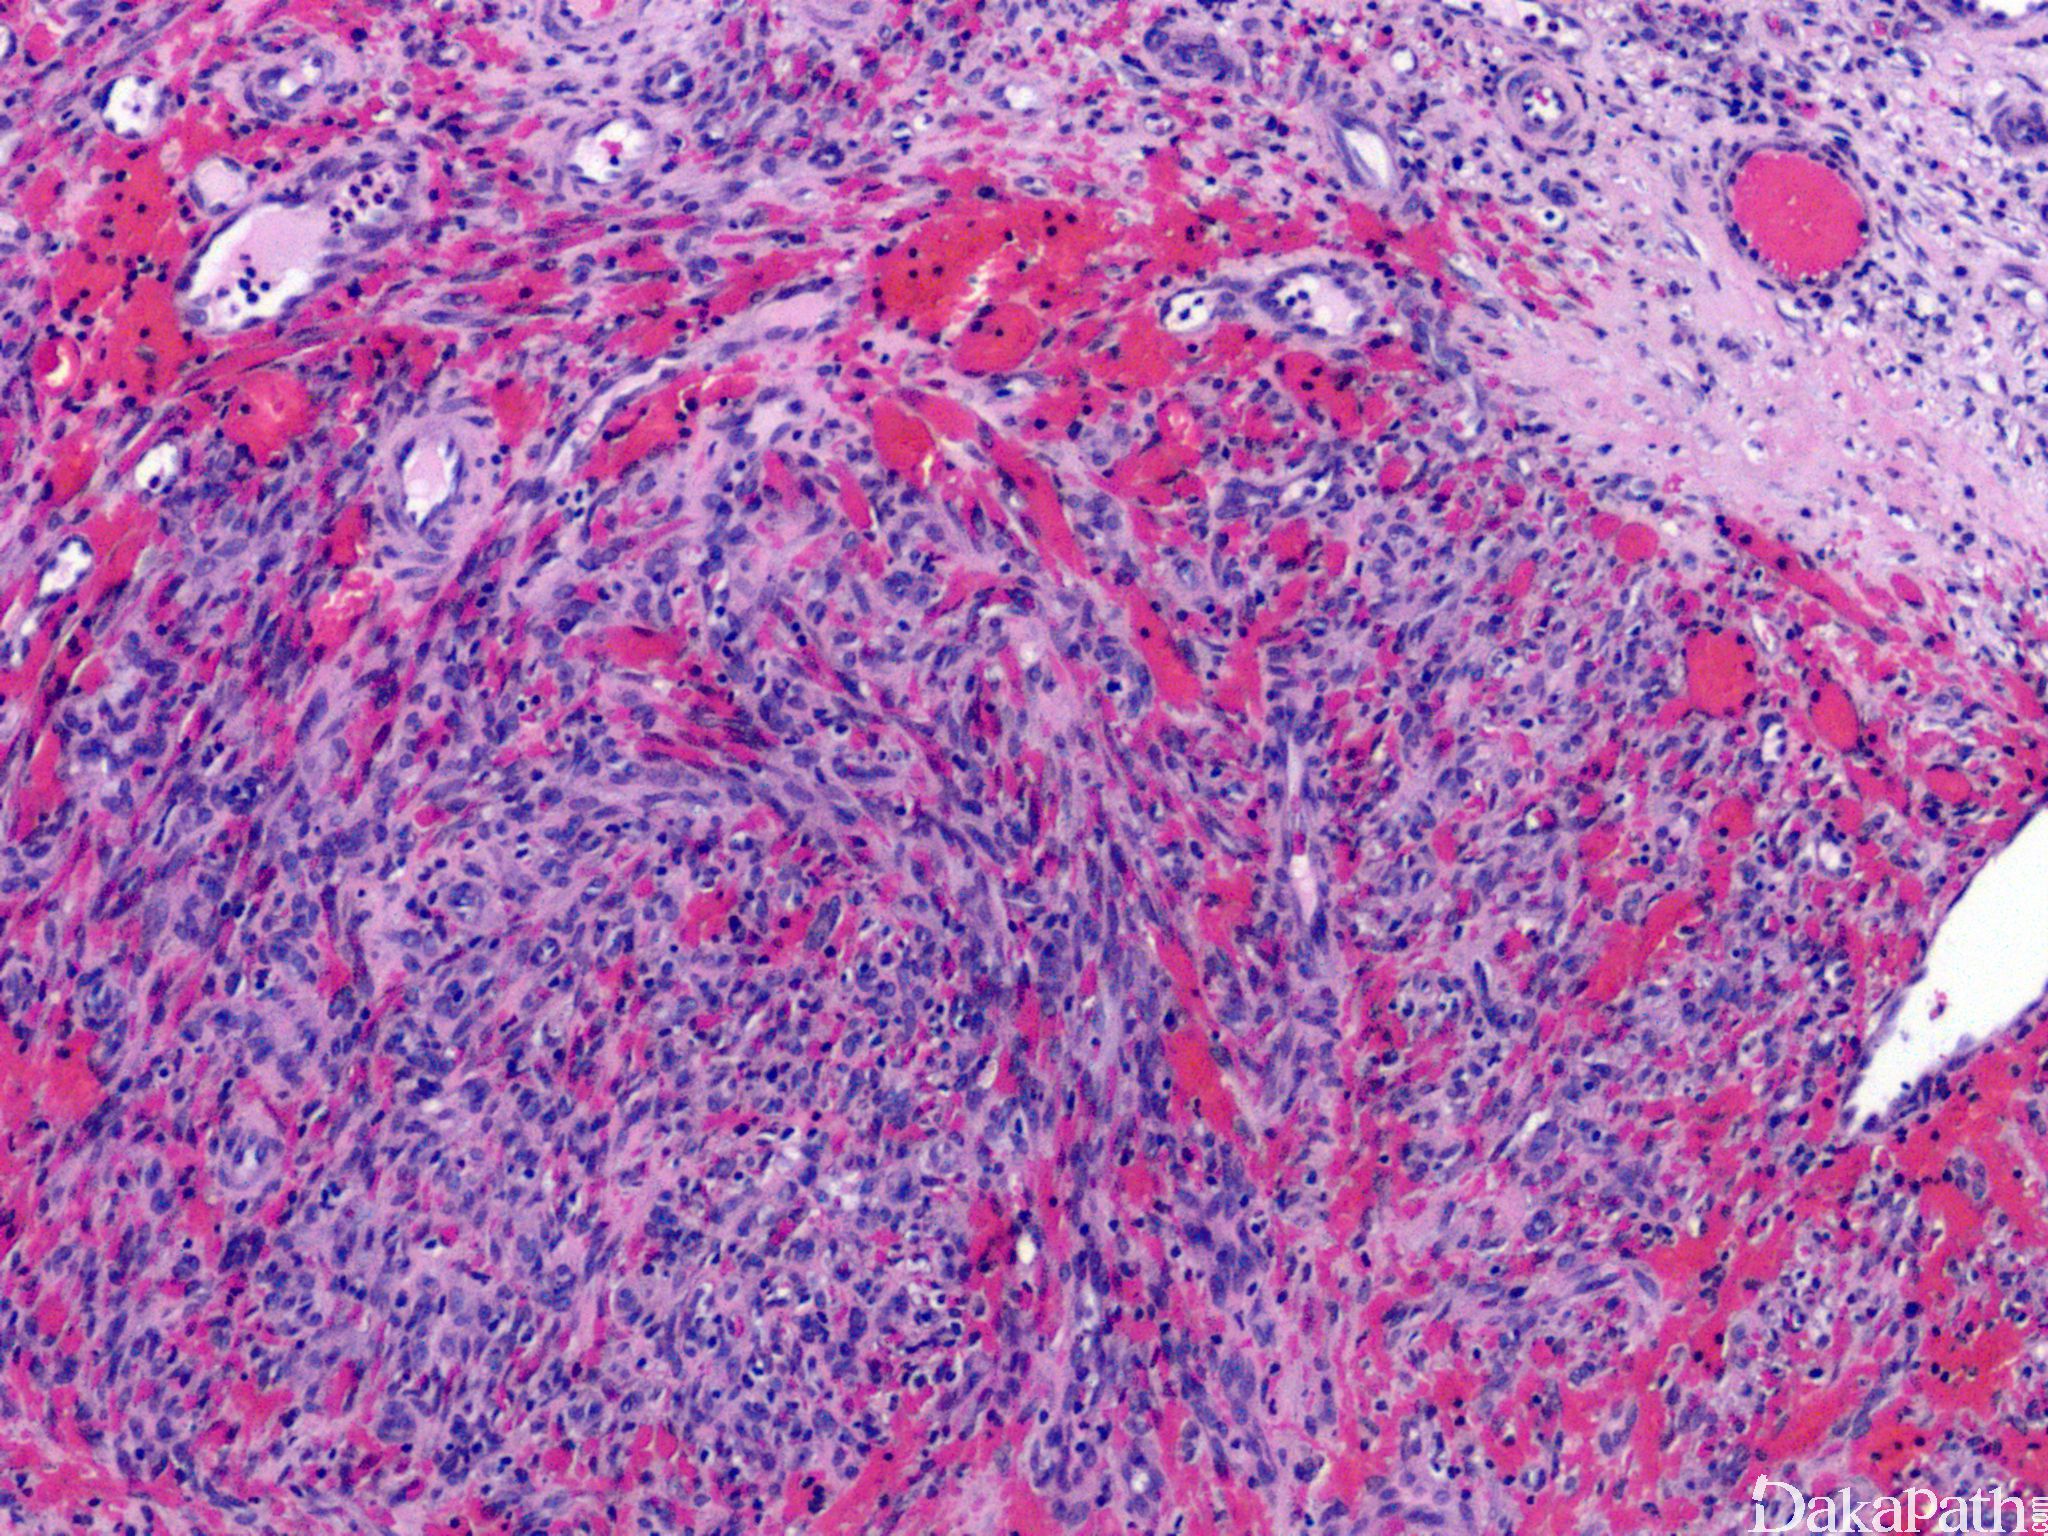

典型的卡波西肉瘤细胞无明显的异型性,核分裂像也不多见,但少数病例中瘤细胞分化较差,异型性明显,可见较多的核分裂像。依据病变进展分为四期:

IV 期为结节期:结节期的病变边界清楚,主要由网状或裂隙状的毛细血管及其周围纵横交错的嗜酸性梭形细胞组成,梭形细胞有一定异型性,核分裂偶见;梭形细胞和血管之间为含有红细胞的裂隙,横切面呈筛孔状或蜂窝状,在梭形细胞内或细胞外可见抗淀粉酶消化 PAS 阳性的嗜伊红色透明小体,结节的边缘常见炎症细胞浸润、含铁血黄素沉着和扩张的血管。 典型的卡波西肉瘤细胞无明显的异型性,核分裂像也不多见,但少数病例中瘤细胞分化较差,异型性明显,可见较多的核分裂像。